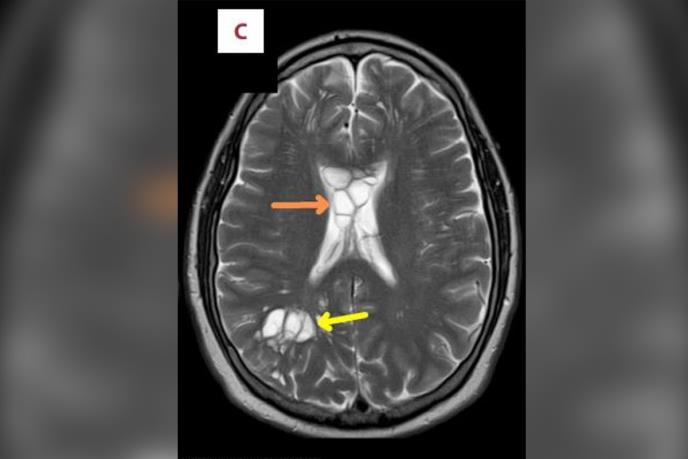

Skeniranje je pokazalo višestruke ciste na obe hemisfere njegovog mozga, kao i otok, za koji su stručnjaci za zarazne bolesti potvrdili da je rezultat svinjske pantljičare koja je položila jaja u njegov mozak i iritirala mu tkivo ispod lobanje.

Rekao je da nedavno nije putovao van zemlje niti jeo sirovu hranu. CT i MRI skeneri su pokazali višestruke ciste na obe strane njegovog mozga. Dijagnostikovana mu je parazitska infekcija neurocisticerkoza.

Stanje se koristi da opiše kada larvalne ciste - zatvorene kese koje sadrže nezreli stadijum parazita - svinjske pantiljičare inficiraju različite delove tela i izazovu upalu.